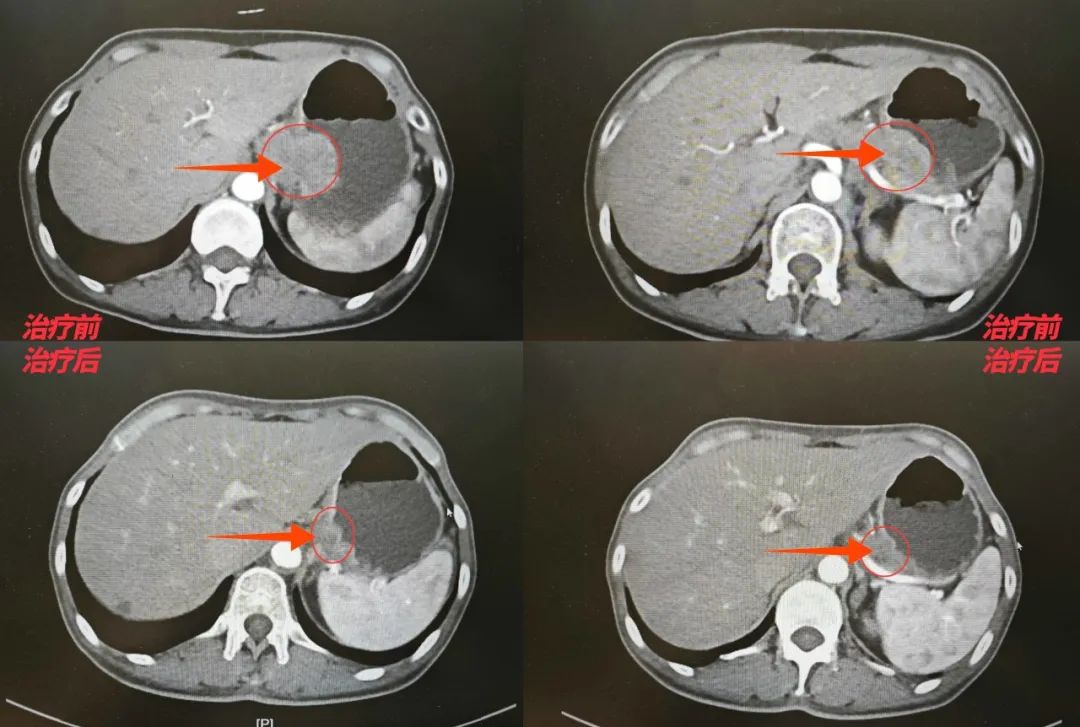

治疗初期,王女士经历了恶心、乏力等副作用,但在肿瘤(胃肠)外科医护团队的全程监护和家人的支持下,她坚持完成了四个周期的化疗。影像复查显示:胃部肿瘤明显缩小,与周围组织的粘连显著改善。

图片